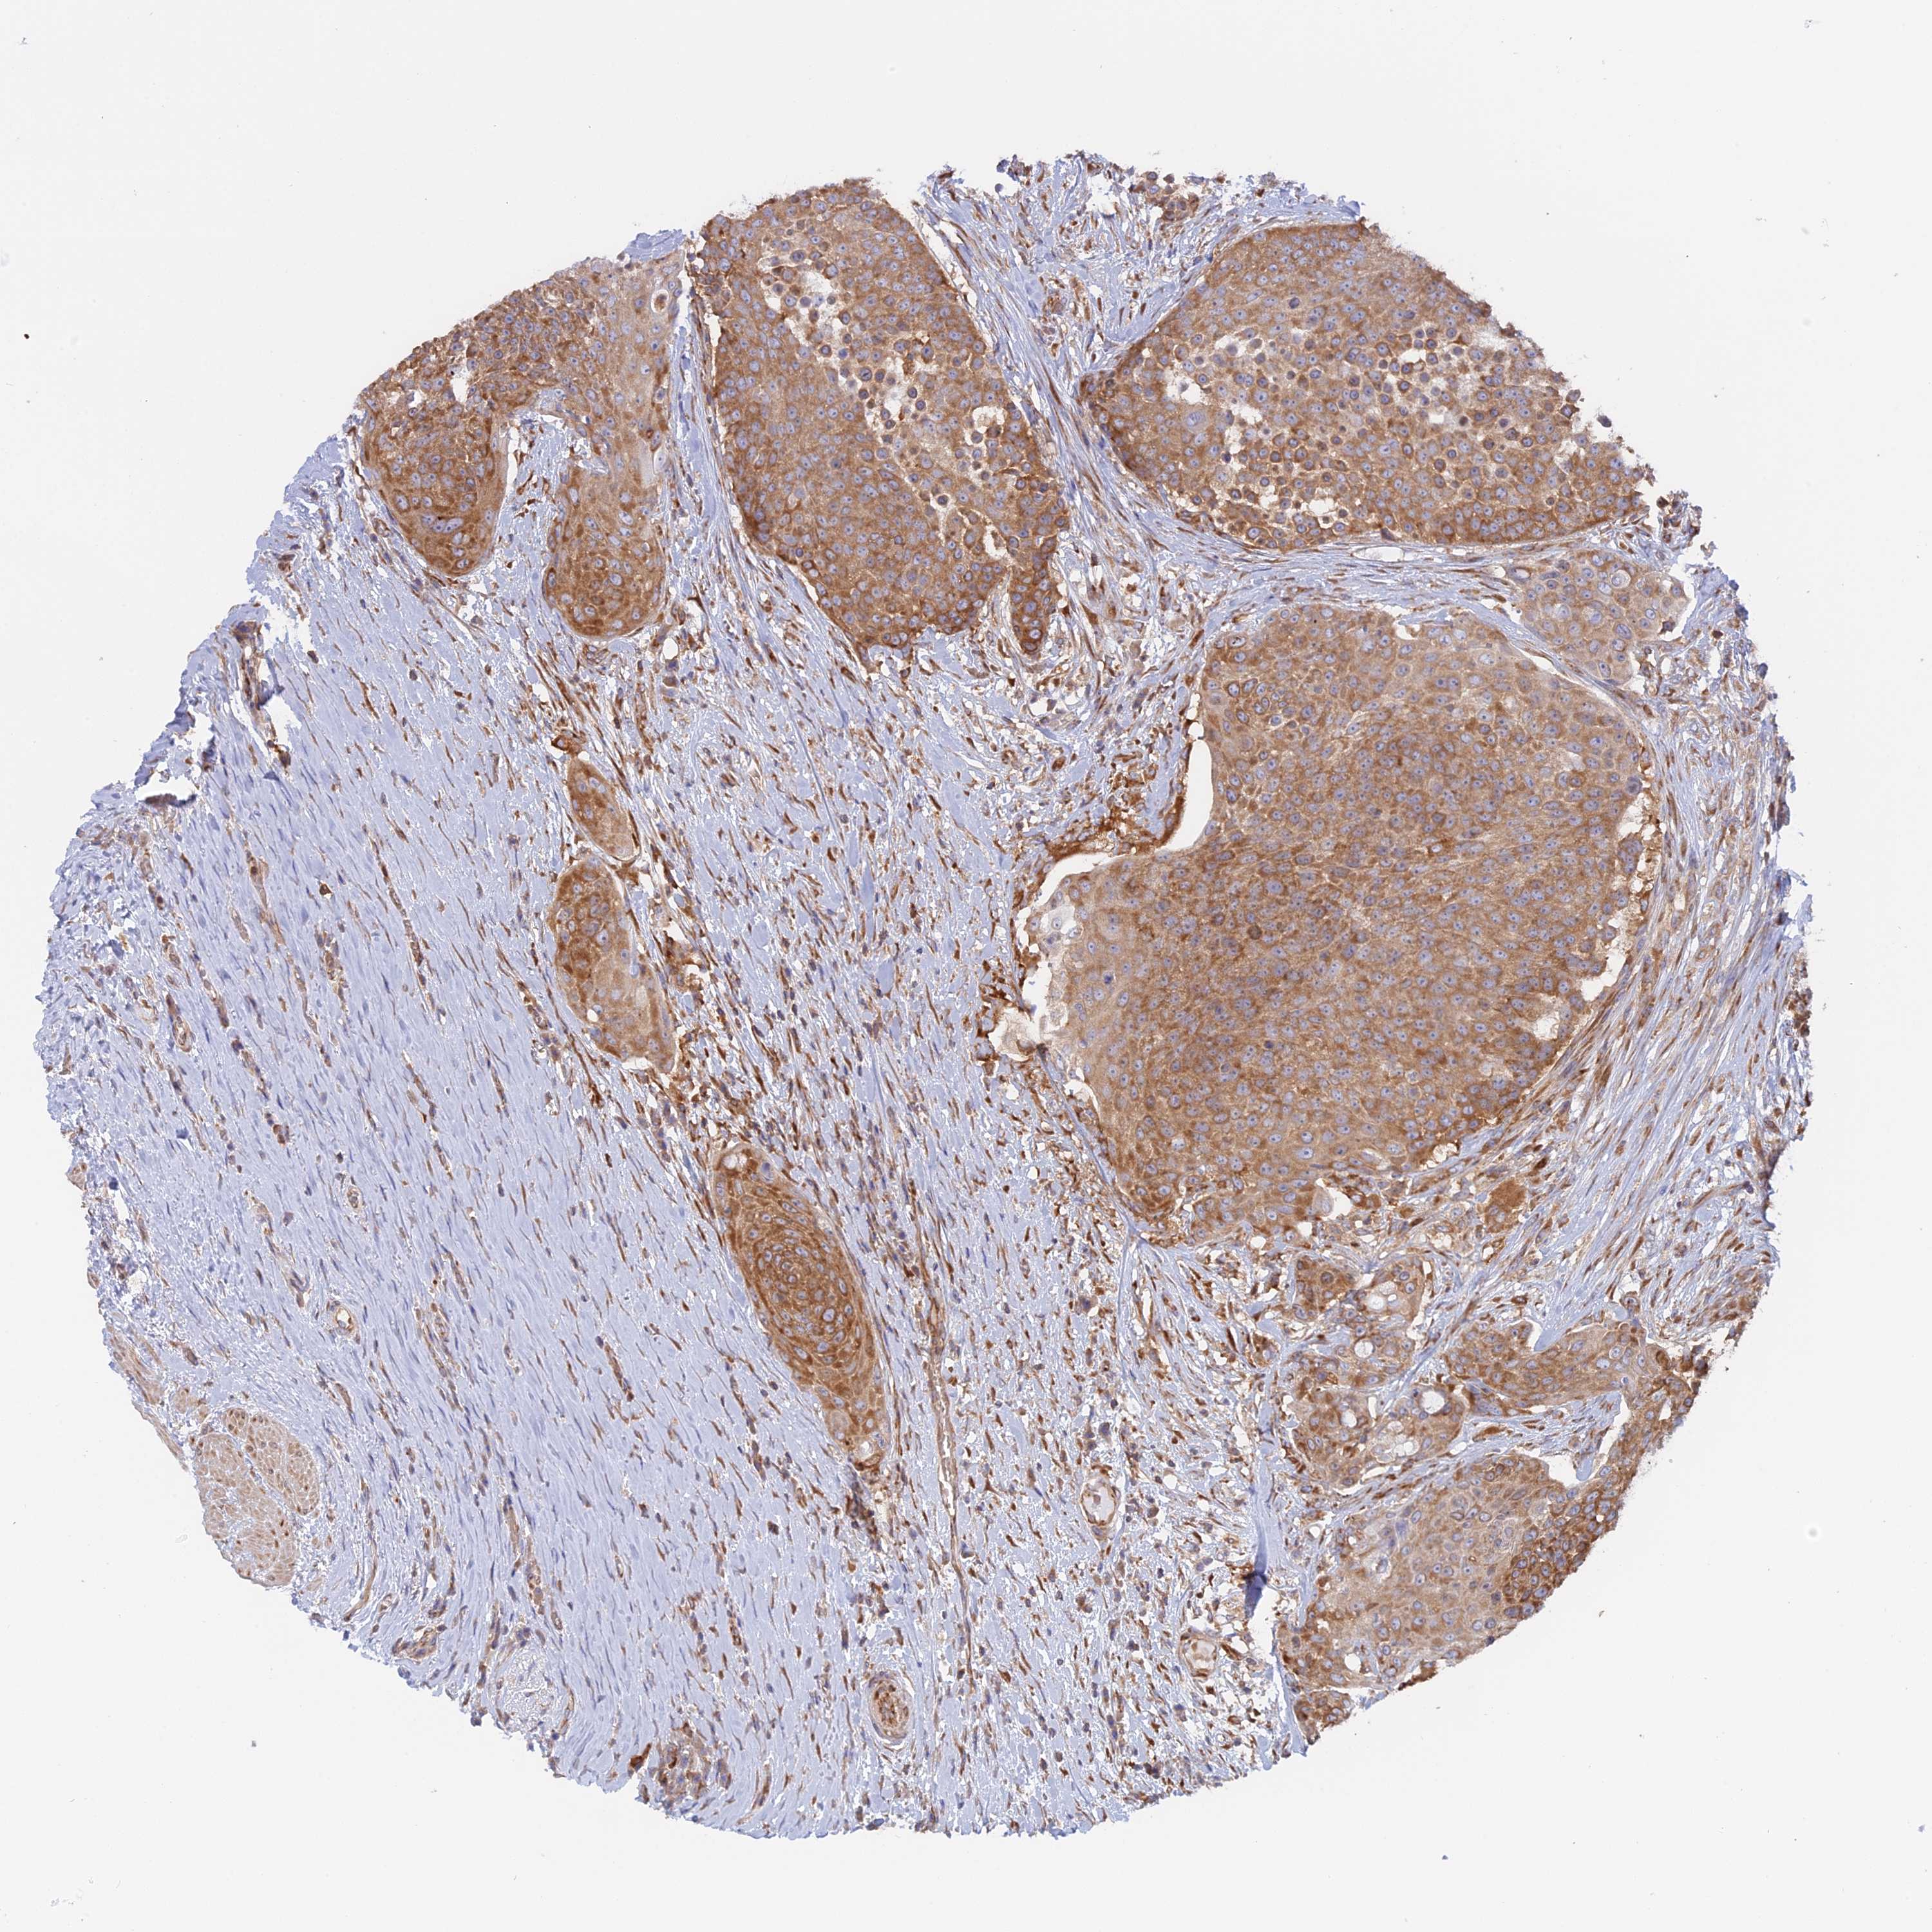

UROTHELIAL CANCER - Protein expressioni

A mouse-over function shows sample information and annotation data. Click on an image to view it in a full screen mode. Samples can be filtered based on level of antibody staining by selecting one or several of the following categories: high, medium, low and not detected. The assay and annotation is described here.

Note that samples used for immunohistochemistry by the Human Protein Atlas do not correspond to samples in the TCGA dataset.

Antibody stainingi

Antibody staining in the annotated cell types in the current human tissue is reported as not detected, low, medium, or high, based on conventional immunohistochemistry profiling in selected tissues. This score is based on the combination of the staining intensity and fraction of stained cells.

Each image is clickable and will lead to virtual microscopy that enables deeper exploration of all samples and also displays staining intensity scores, fraction scores and subcellular localization as well as patient and tissue information for each sample.

Antibody HPA042484

Antibody HPA045481

Staining

High

Medium

Low

Not detected

Intensity

Strong

Moderate

Weak

Negative

Quantity

>75%

75%-25%

<25%

None

Location

Nuclear

Cytoplasmic/membranous

Cytoplasmic/membranous,nuclear

Urothelial carcinoma, High grade

Urothelial carcinoma, Low grade

Urothelial carcinoma, NOS